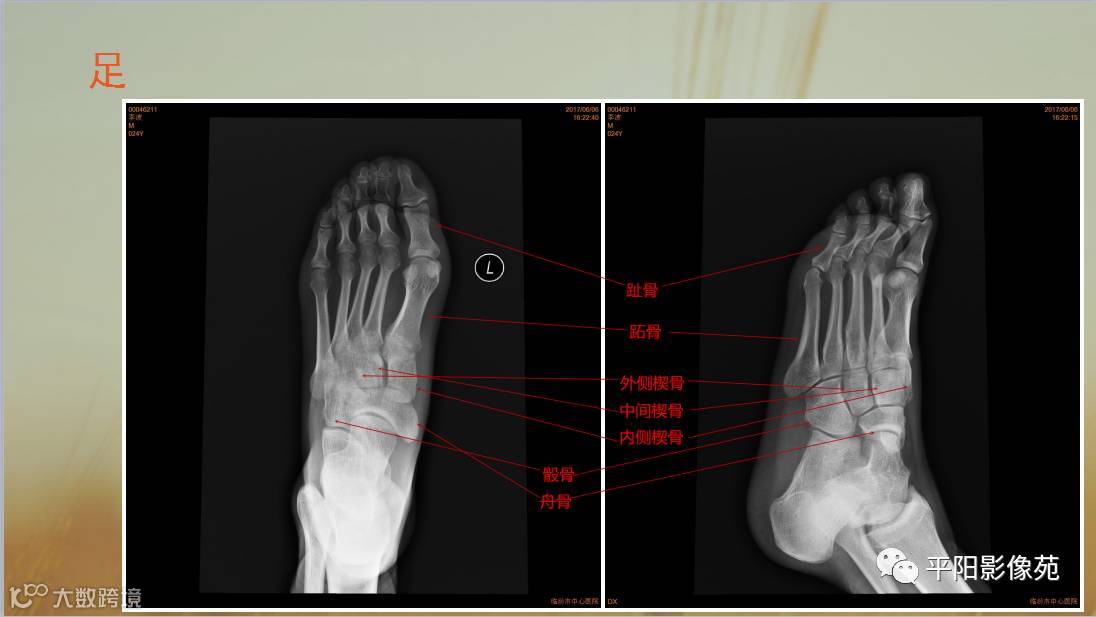

四肢骨骼X线解剖